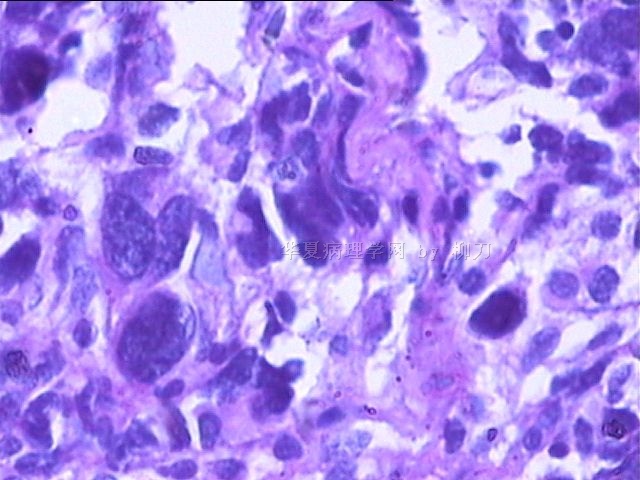

女,34y,头痛一月,右额叶占位:5*5*4cm。囊性区域,4cm。大体:3.5x3x1cm灰白间暗褐色组织一堆,质嫩。临床诊断1:胶质瘤,2:血管母细胞瘤。

本人县级医院头颅手术少,考虑胶质母细胞瘤。大家指导指导。

胶母

同意胶质母细胞瘤。细胞异型、坏死、核分裂、血管内皮肿胀增生均可见到。

This is certainly a WHO grade IV malignant neoplasm. While most likely a glioblastoma, I would carefully rule out PNET by staining for GFAP and neuronal markers such as synaptophysin, NeuN and NSE. Rarely, PNET may shows marked pleomorphism and indistinguishable from glioblastoma on HE stain.

同意马老师的意见,该肿瘤从形态及年龄来看考虑PNET或GBM,须标记Syn、NSE、S-100、NeuN和GFAP来鉴别。

结合图片细胞形态特点考虑胶质母细胞瘤,组化标记排除其他